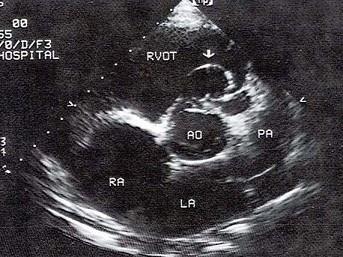

该病例最可能的诊断?(?)A.右室流出道狭窄B.室间隔缺损C.主动脉右冠窦瘤破裂D.主动脉右冠瓣脱垂E.房间隔膨出瘤

问题 该病例最可能的诊断?(?)

选项 A.右室流出道狭窄 B.室间隔缺损 C.主动脉右冠窦瘤破裂 D.主动脉右冠瓣脱垂 E.房间隔膨出瘤

答案 C